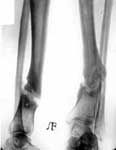

1.Ложный сустав нижней трети большеберцовой кости